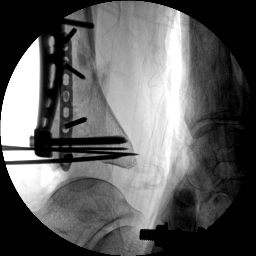

1.CO外固定半環連接跟骨穿針并通過CO接骨機器人配套的連接桿與CO接骨器人中間機械臂相連,調整機械臂,進行骨折端初步復位,C臂確認復位滿意,關節間隙拉開。

2.CO接骨機器人持續牽引維持復位,選擇前外側切口對前外側骨塊進行撬撥復位,并用克氏針進行臨時固定。C臂透視復位滿意,放置兩塊鋼板進行固定。

3.在脛骨近端穿入一根克氏針,連接CO外固定架進行固定,并外踝處穿入一根克氏針進行固定。C臂透視位置滿意,縫合結束手術。